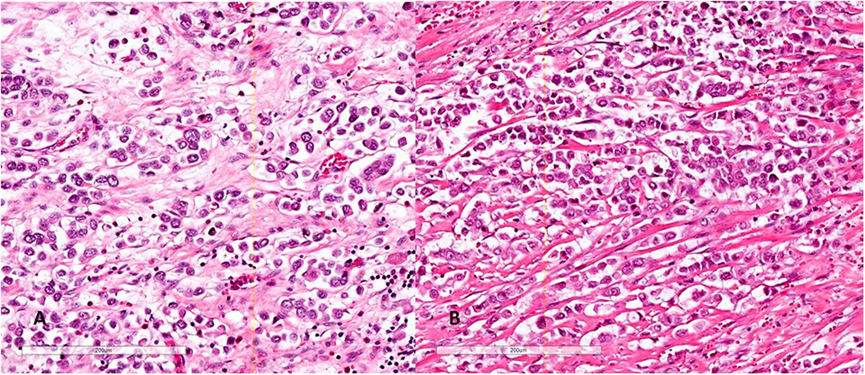

图1A、1B. PUC的特征是散在的、核偏心位和具有嗜酸性胞质的瘤细胞,呈浆细胞样外观

图2A. 肿瘤细胞排列成巢或列兵样;图2B酷似炎症,瘤细胞极具欺骗性

现在文献中没有详细报道PUC的肉眼所见,仅描述该肿物无蒂,呈突起性生长,可单发或多发,以及膀胱的弥漫性浸润。关于PUC的定义现在尚未统一,大多数研究者认为,如果病灶中至少有50%~90%的肿瘤细胞呈浆细胞样时,即可称为浆细胞样尿路上皮癌;但有些研究者则认为只要肿瘤呈浆细胞样即可,不用理会其所占百分比。PUC是一种高级别尿路上皮癌。肿瘤细胞小至中等大,粘附性差,核偏心位,椭圆形至圆形,核染色质深染。胞质中等量或丰富,嗜酸性,形态类似于浆细胞。双核罕见,核分裂象常见。核仁虽可以识别,但在大多数病例中并不显著。

PUC中大约有一半是纯粹的浆细胞样尿路上皮癌,但也可以伴发于经典的尿路上皮癌、肉瘤样尿路上皮癌、微乳头状尿路上皮癌,巢状尿路上皮癌和小细胞癌。细胞排列成条索状,列兵样,小巢状,实性成片,偶尔会呈现欺骗性的良性外观,从而误诊为炎症。间质可能呈黏液样外观,并可见胞质内空泡,但并不是真正的印戒细胞。在30%–43%的病例中存在血管浸润。在现在报道的病例中,肿瘤分期为pT3或更高的PUC占56%~100%,淋巴结转移为20%~73%。PUC呈弥漫性浸润生长模式,可沿骨盆筋膜平面局部播散,累及骨膜、直肠周围和输尿管周围软组织,腹膜播散发生在33%至68%患者。